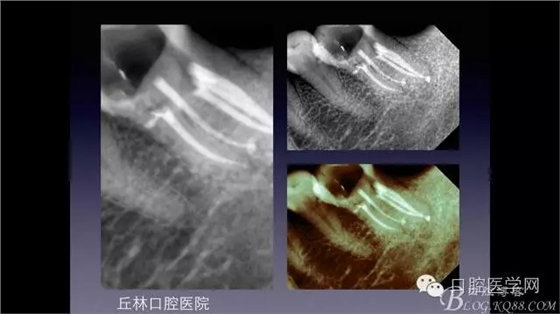

一例36根管再治療,五個根管冷側(cè)加壓病例